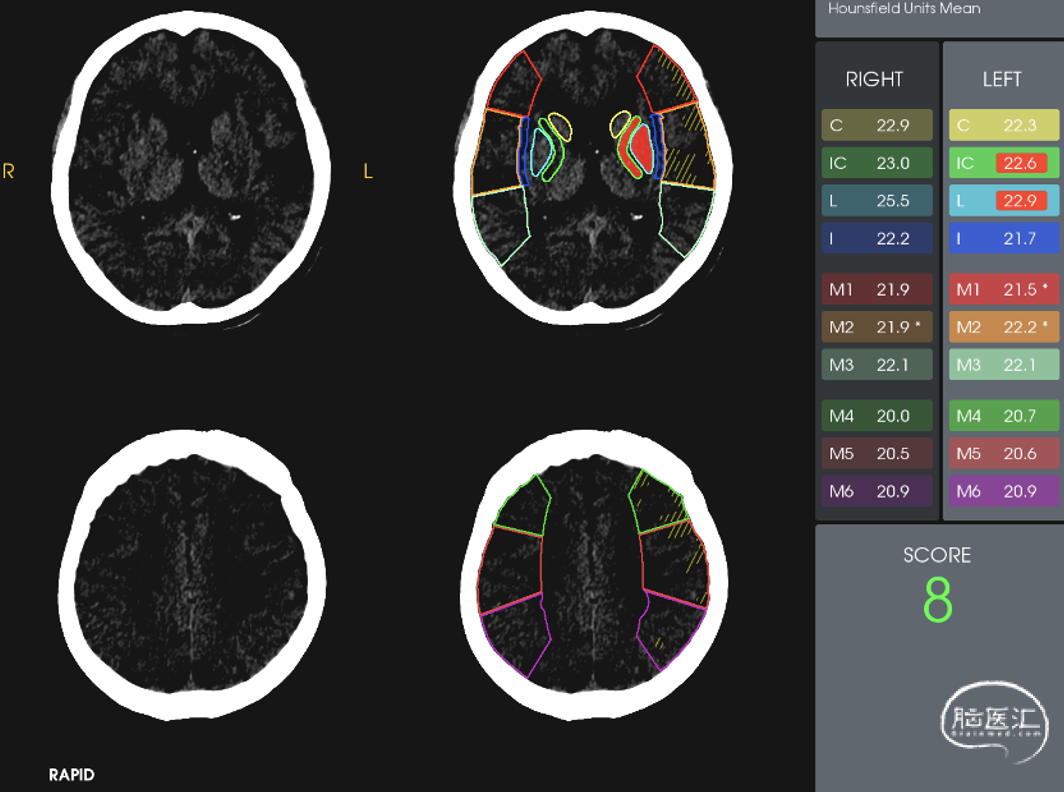

患者醒后卒中,依据指南应在多模式影像学评估下选择最佳治疗方案,急诊绿道完成了一站式RAPID软件AI影像处理。

CTP提示左侧大脑半球大面积低灌注区。

发病超过6h的患者,应利用脑灌注成像技术,明确存在大面积缺血半暗带。患者家属积极并同意治疗。

1.患者高龄,但发病前生活质量较好。本次为醒后卒中左侧大脑中动脉急性闭塞,临床症状较重,基于多模CT及RAPID评估,仍有较大缺血半暗带可以挽救,征得患者家属知情同意后,急诊行脑血管造影+左侧大脑中动脉取栓术,获得了较为满意的预后。